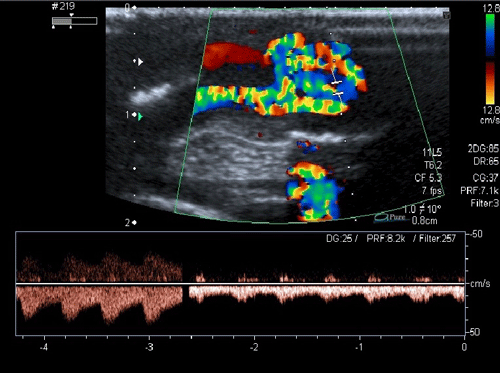

A 20-day-old male neonate with an umbilical hernia was referred to our hospital because of persistent wet umbilicus. Umbilical examination showed a 2 cm diameter umbilical hernia and a long epithelialized pulsatile cord with granulomatous tissue at its end (Fig. 1). Palpable thrill was note at the midportion of the umbilical cord. Doppler ultrasonography revealed a mass at the end of the umbilical cord harboring dilated blood vessels with turbulent blood flow (Fig. 2). This vascular mass continued to the umbilical vein, which was dilated and flowed into the liver. Abdominal contrast-enhanced computed tomography revealed umbilical AVM; the umbilical arteries were patent from both internal iliac arteries, flowed into the mass directly at the end of the umbilical cord, and the dilated umbilical vein flowed out from the mass, continuing from the umbilicus to the umbilical part of the portal vein in the liver (Fig. 3, 4).

Figure 2: Dilated blood vessels showing turbulent bloodstreams. |